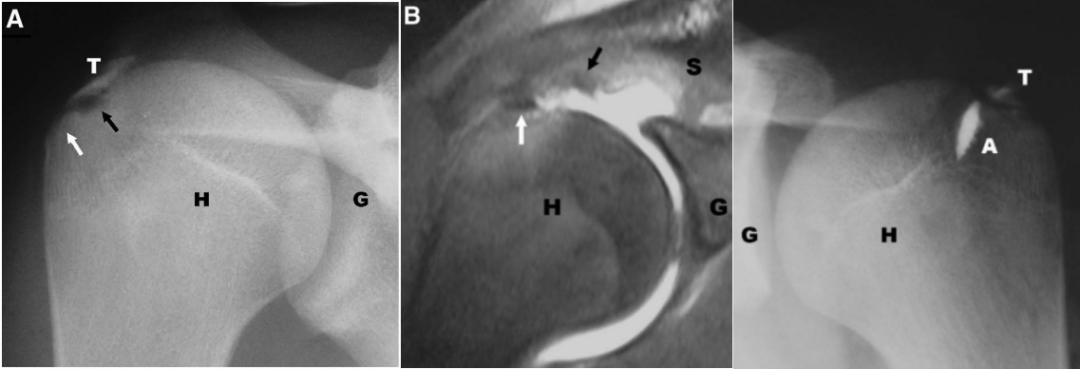

肱骨大结节骨折 ORIF,术前 X 线片显示肱骨大结节骨折情况;术中暴露肱

肱骨大结节骨折 ORIF,术前 X 线片显示肱骨大结节骨折情况;术中暴露肱